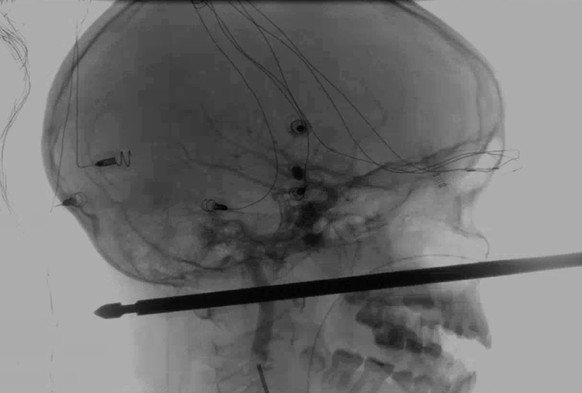

Der zehnjährige Xavier Cunningham fiel vergangenes Wochenende zuhause im US-Bundesstaat Missouri von einem Baum und landete mit dem Kopf auf einem Fleischspiess. Dieser durchdrang seinen Schädel vom Gesicht bis zum Hinterkopf. Der Knabe wurde beim Spielen im Baumhaus von mehreren Wespen überrascht, weshalb er die Kontrolle verlor.

Im Universitätsspital von Kansas folgte die Operation. «Man hätte es nicht besser treffen können», sagte Koji Ebersole, der Chef-Neurochirurg des Spitals. «Die Chancen standen eins zu einer Million, dass der Spiess 15 bis 18 Zentimeter durch die Vorderseite des Gesichts nach hinten ging und diese Dinge nicht traf.»

Tatsächlich verfehlte der Spiess Augen, Gehirn, Rückenmark und die wichtigsten Blutgefässe komplett. Letztlich war es aber auch ein Meisterwerk der Mediziner, dass Xavier heute schon wieder ziemlich gut auf den Beinen ist. Da der Spiess quadratisch war, musste jegliche Drehbewegung bei der Entnahme vermieden werden. Die scharfen Kanten hätten weitere Verletzungen herbeiführen können.